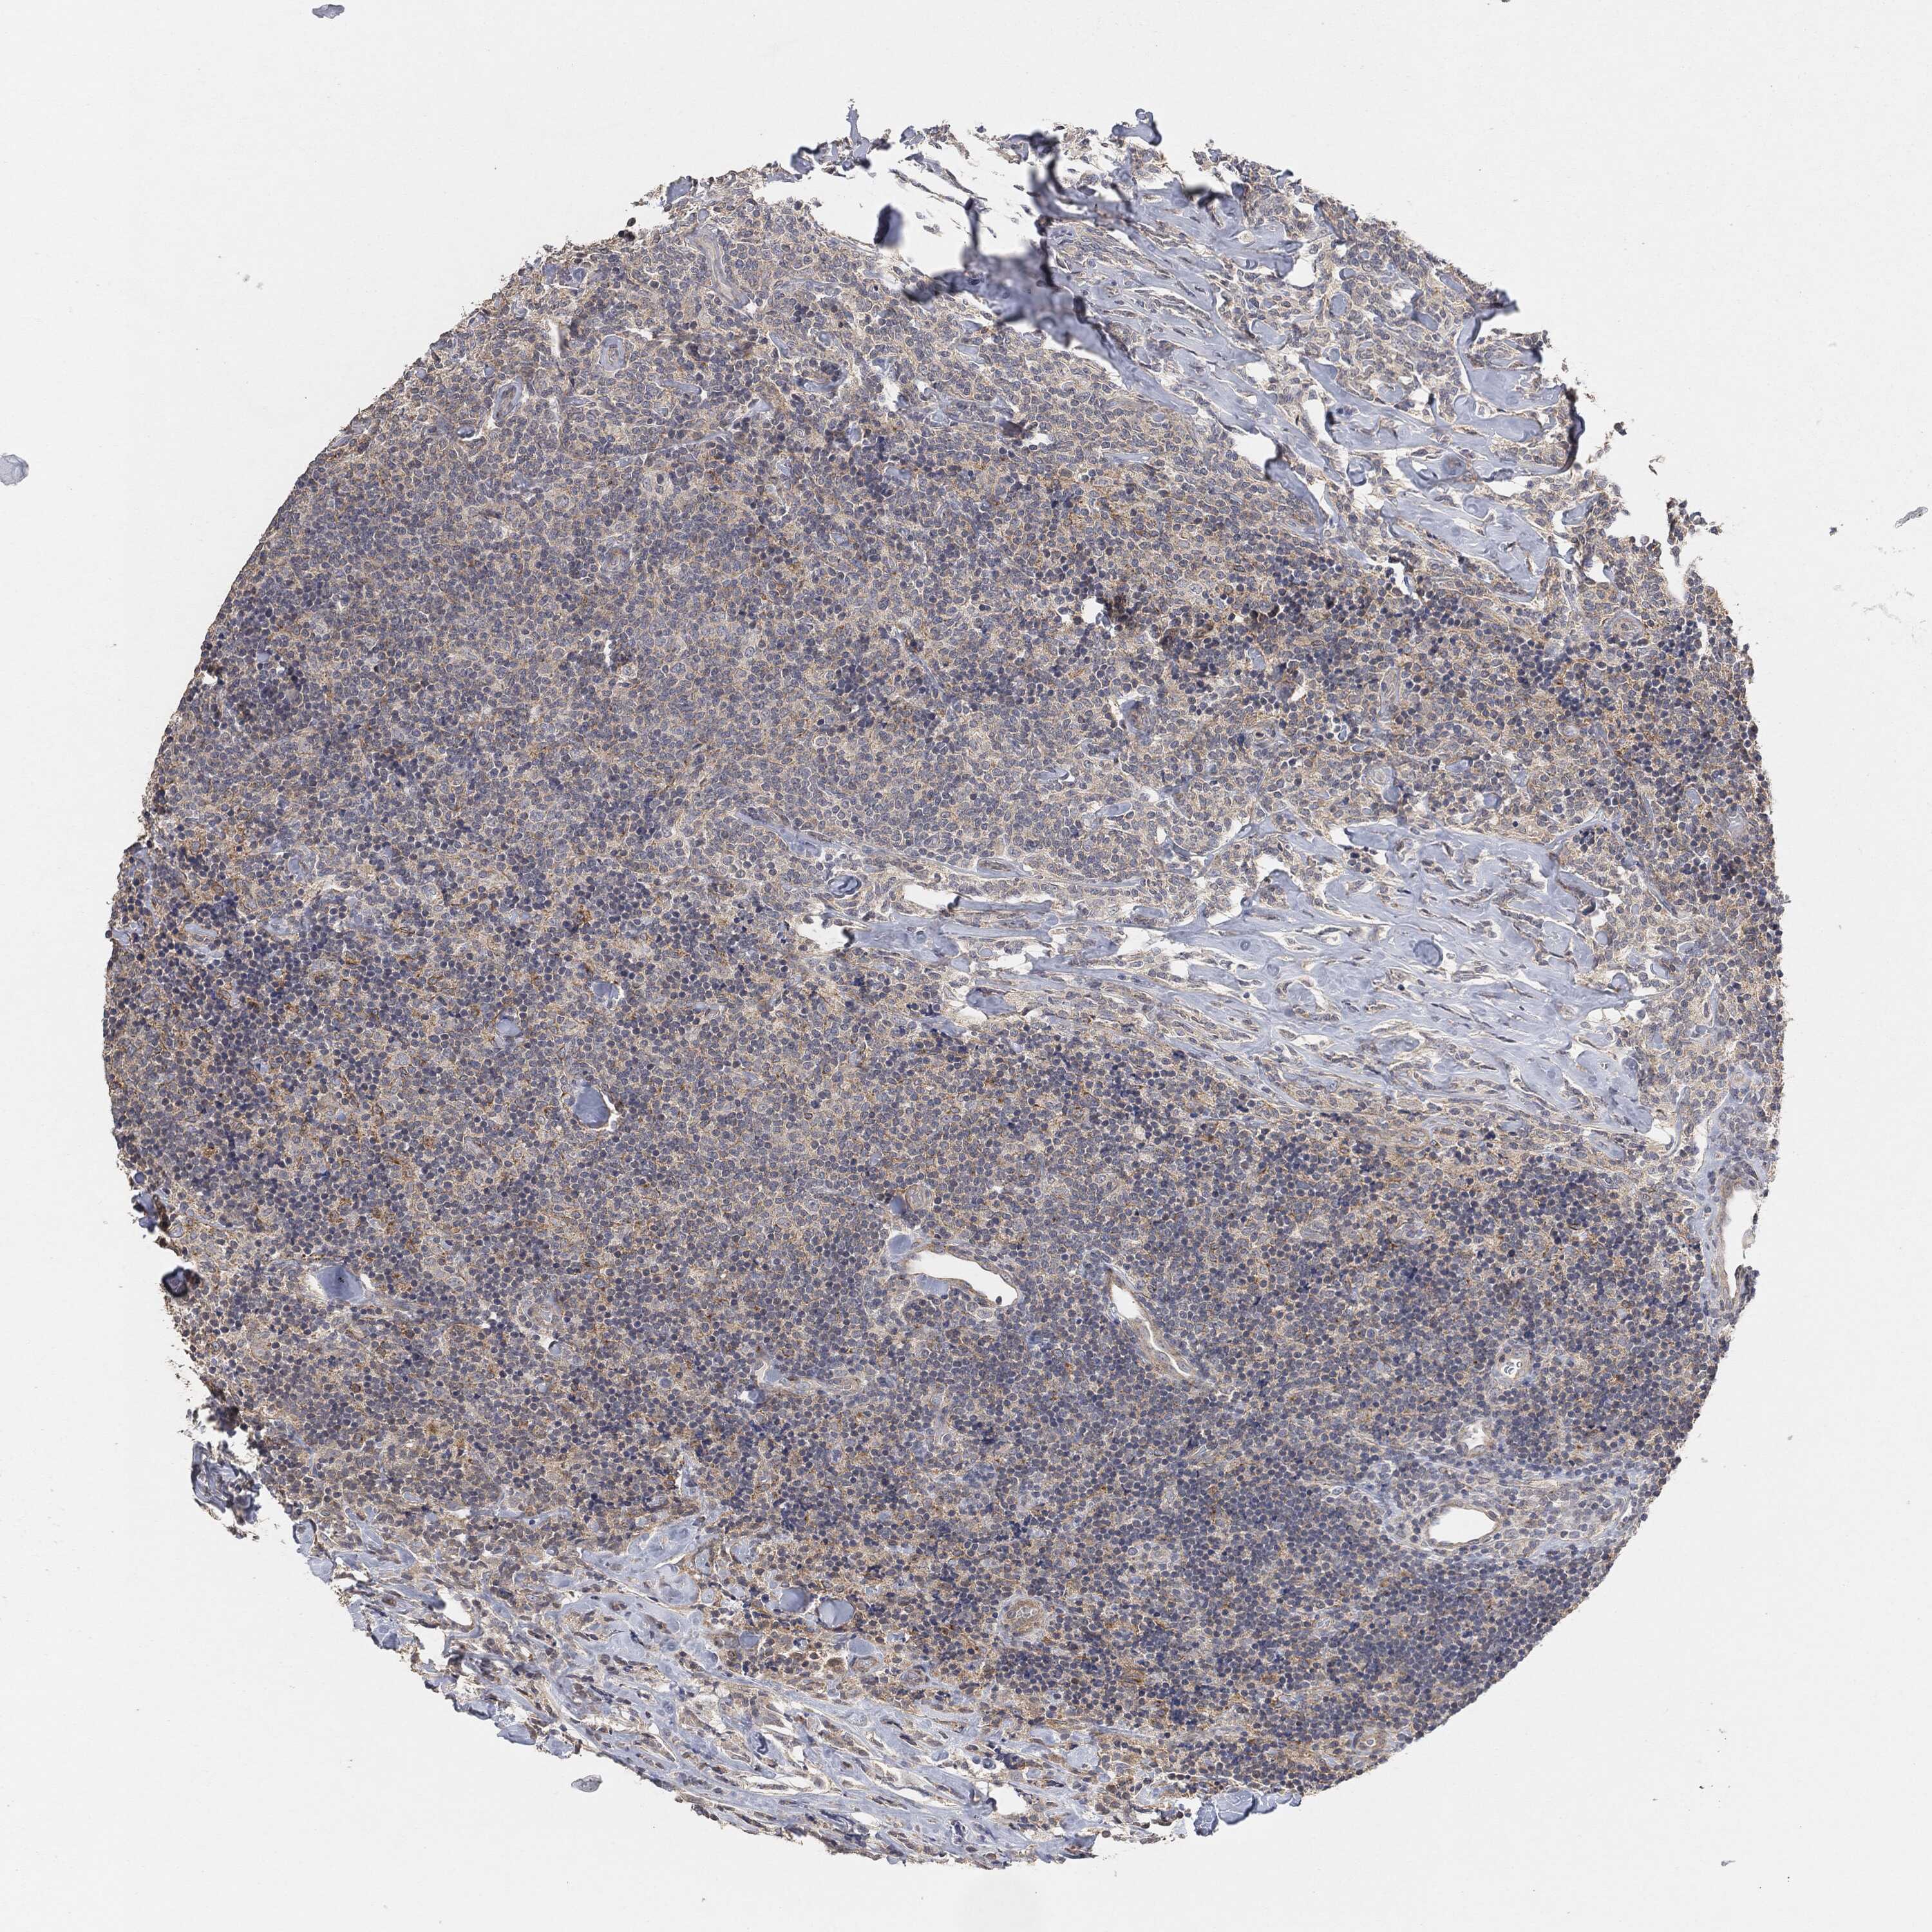

LYMPHOMA - Protein expressioni

A mouse-over function shows sample information and annotation data. Click on an image to view it in a full screen mode. Samples can be filtered based on level of antibody staining by selecting one or several of the following categories: high, medium, low and not detected. The assay and annotation is described here.

Antibody stainingi

Antibody staining in the annotated cell types in the current human tissue is reported as not detected, low, medium, or high, based on conventional immunohistochemistry profiling in selected tissues. This score is based on the combination of the staining intensity and fraction of stained cells.

Each image is clickable and will lead to virtual microscopy that enables deeper exploration of all samples and also displays staining intensity scores, fraction scores and subcellular localization as well as patient and tissue information for each sample.

Malignant lymphoma, non-Hodgkin's type, High grade

Hodgkin's disease, NOS

Malignant lymphoma, non-Hodgkin's type, Low grade